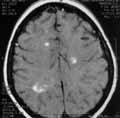

см. На Т1-взвешенном изображении поля, выявляемые на Т2-изображении дают

слабо пониженный МР-сигнал или изоинтенсивны (Рис. 2); киста дает

гипоинтенсивный сигнал, четко контурируется. После введения магневиста

очаги, не визуализирующиеся на Т1-изображении, проявили себя равномерным

усилением МР-сигнала, другие дали усиление в виде ободка и небольшого усиления

в центре (Рис. 3).

Рис. 2. Т1-взвешенное изображение. Очаги, выявляющиеся на Т2-изображении, изоинтенсивны или слабо гипоинтенсивны. В левой лобной доле киста элипсовидной формы. |

Киста не отреагировала на введение контраста. Центральные отделы гранулематозных

полей, представленные зонами некроза на Т2-изображении более гиперинтенсивны,

на Т1-изображении гипоинтенсивны и после введения контраста его не накапливают,

усиление сигнала идет в периферических отделах в виде ободка. Не резко

расширены тела боковых желудочков. Срединные структуры не смещены.